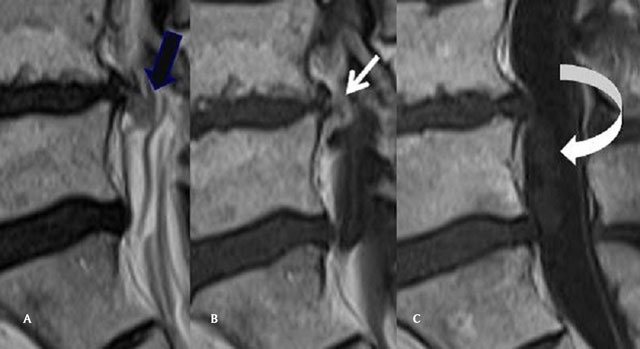

Figure 1

(A) Sagittal T2 Mri of the lumbar spine: Continuity of the disc and the upper part of the disc herniation (back arrow). (B) Sagittal T1 Mri of the lumbar spine, after gadolinium injection. The upper part of the disc is compact with peripheral contrast enhancement (white arrow). (C) Sagittal T1 Mri of the lumbar spine, after gadolinium injection. The intradural component of the IDH does not enhance (curved arrow).